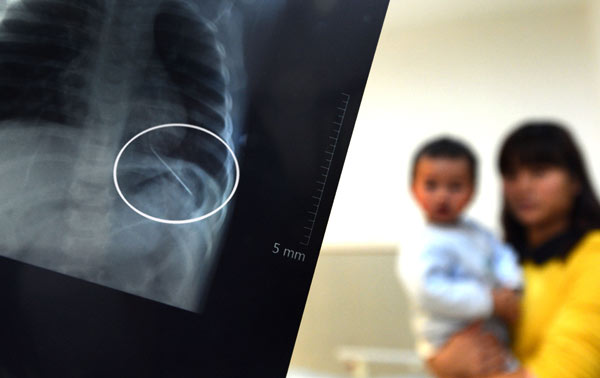

An X-ray shows a needle that was found inserted into the left lung of a 14-month-old boy in Nanjing, Jiangsu province, on Monday. Shi Xianghui / For China Daily

A mother in Nanjing, Jiangsu province, reported to police that her 14-month-old baby was attacked, after doctors removed a 5-centimeter-long needle from the boy's lung on Monday.

Doctors took an X-ray of his chest and were shocked to find a needle-shaped metal object in his lung.

"It was dangerous because the pinpoint was positioned outside the lung and could have moved toward the heart," Mo said.